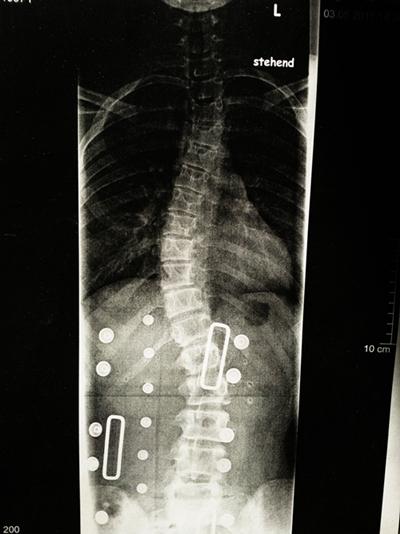

edit: hab jetzt das neue röntgenbild mal angehangen,wiegesagt ich glaub nich dass ihr damit etwas anfangen könnt. :S

keine ahnung wieviel grad, ich weiß garnichts. :(

Foto6410.jpg (26.65 KiB) 9100 mal betrachtet

Dein Röntgenbild ist doch gut zu erkennen. Wäre nur schön, wenn wir auch noch ein älteres Röntgenbild hätten, um vergleichn zu können. Für mich ist das eine Skoliose und keine C-Skoliose. Die Kyphose scheint bei dir nur eine nebensächliche Rolle zu spielen, weil davon anscheinend kein Röntgenbild existiert. Lass dein RöBi bitte ausmessen, ich kann das leider nicht.

Ich finde schon, dass man mit deinem Röbi was anfangen kann. Wir wissen nun zumindest, dass sich die 48° auf die Skoliose beziehen. Das Problem ist nur, nach sehr viel weniger sieht es auch nicht auf diesem Bild aus. Daher kann ich dir wirklich nur ans Herz legen, unbedingt in nächster Zeit nochmal jemanden drauf gucken lassen, der beurteilen kann, ob´s tatsächlich nicht besser geht oder ob es irgendwelche Mängel am Korsett gibt und man dies mit einem besseren Korsett hinbekommt. Zu Nahr habt ihr es ja nicht so weit. Ich würde an deiner Stelle auch nicht mehr all zu lange damit warten, denn 48° sind schon viel und wenn da das Korsett nicht ordentlich korrigiert kann sich das ganz schnell weiterverschlechtern.